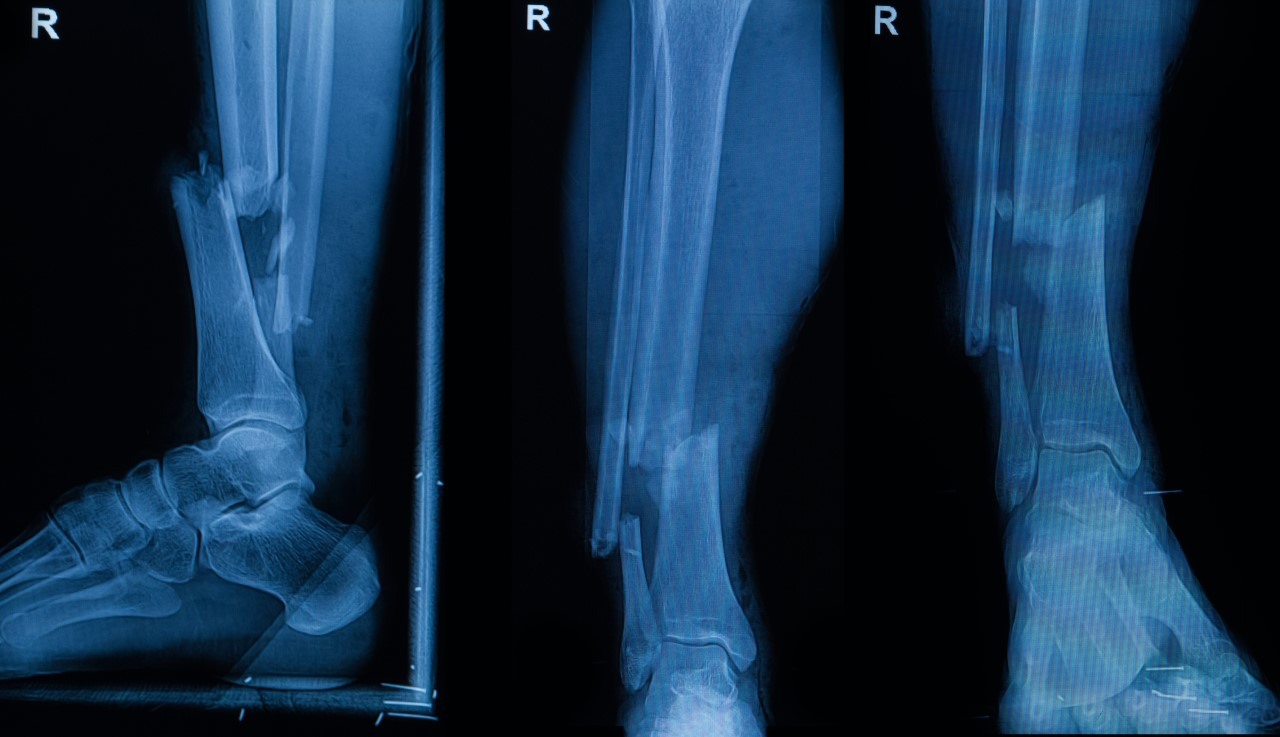

Predstavme si situáciu: vodič bez pásu havaruje v meste rýchlosťou 50 km/h. Následky: zlomeniny rebier, zápästia, otras mozgu, tržné rany na tvári. Nie je to fatálna nehoda, ale typická „mestská búračka“. 6 až 12 týždňov strávených na PN je realistické rozpätie pri takýchto zraneniach (pri komplikáciách aj viac).

1. Diagnostika po prijatí do nemocnice

- CT hlavy: 85 €

- CT hrudníka: 110 €

- RTG zápästia: 20 €

- CT polytrauma balík (ak sa spraví komplet): 345 €

Diagnostika spolu: cca 500 – 600 €

2. Chirurgické zákroky

- Ošetrenie tržných rán na tvári: 150 €

- Operácia zlomeniny zápästia (skrutky, platničky – ORIF): 2265 €

- Stabilizácia zlomených rebier (konzervatívne, bez operácie, ale so sledovaním): 0 € navyše za zákrok, ale pripočítava sa hospitalizácia

Zákroky spolu: cca 2400 €